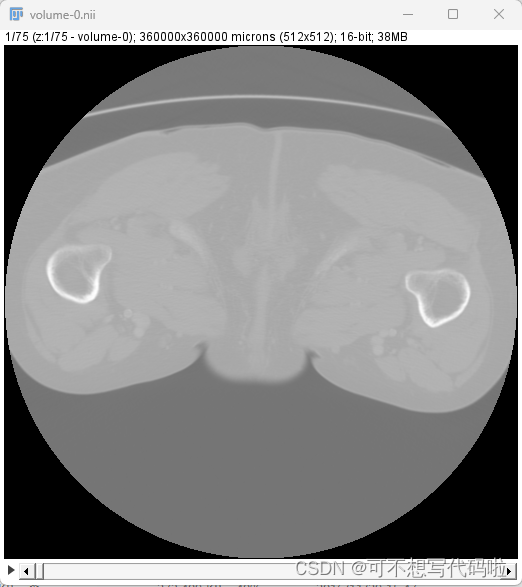

把要查看的图像直接拖进ImageJ也可以查看。不过就只有一个z轴视图可以看,我觉得如果是快速浏览做二维分割也够用了。文件拖进来后有如下页面,不用管直接点OK。

然后就能看到这样的二维视图。拖动最下方的条可以手动调整查看位置,或者使用左下角的播放按钮自动顺序播放。